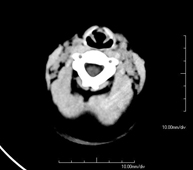

- Neurorradiología- TC Cráneo Prueba radiológica que consiste en obtener imágenes del cráneo de alta definición anatómica (tronco cerebral, cerebelo, cerebro, calota craneal, etc.), mediante el empleo de un equipo de TC (Tomografía Computarizada).Indicaciones: traumatismos, cefalea, trastornos de la memoria, pérdida de fuerza súbita en una extremidad o mitad del cuerpo. Prueba radiológica que consiste en obtener imágenes del cráneo de alta definición anatómica (tronco cerebral, cerebelo, cerebro, calota craneal, etc.), mediante el empleo de un equipo de TC (Tomografía Computarizada).Indicaciones: traumatismos, cefalea, trastornos de la memoria, pérdida de fuerza súbita en una extremidad o mitad del cuerpo.